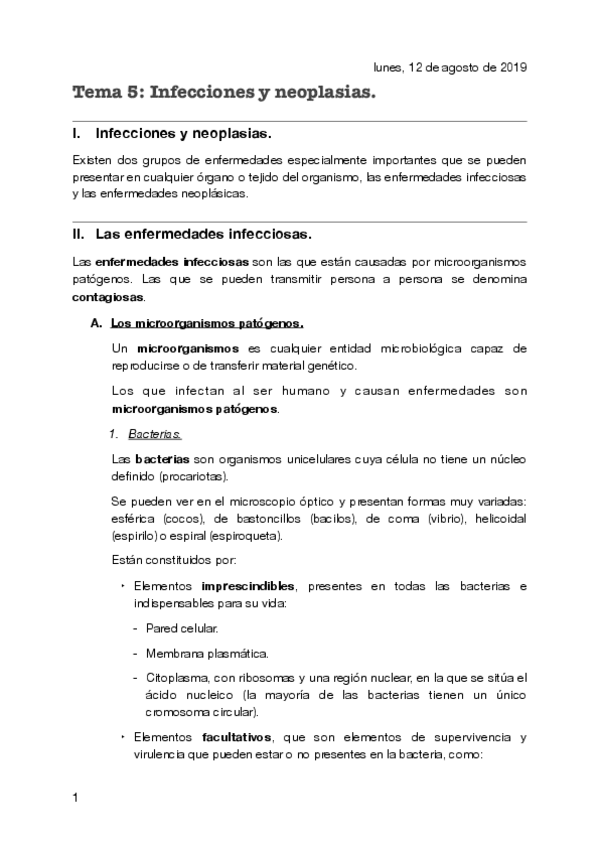

He publicado nuevos apuntes de Fisiopatología general: Tema-5-infecciones-y-neoplasias.pdf